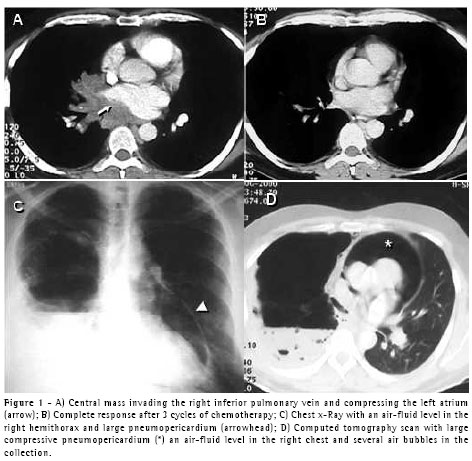

A 40-year-old male patient with atrial fibrillation was seen by a cardiologist. He was a nonsmoker and his chest X-rays showed hilar adenopathy in the right lower lobe. A computed tomography (CT) scan revealed a central mass invading the inferior pulmonary vein and compressing the left atrium (Figure 1A). An endobronchial lesion was seen in the right lower lobe bronchus, and a biopsy was performed. The results were consistent with neuroendocrine large cell carcinoma. The patient was submitted to three cycles of cisplatin-based chemotherapy and radiotherapy. Subsequent CT scans (Figure 1B) and bronchoscopic examinations revealed a highly positive response to the treatment. He was submitted to radical right pneumonectomy including a portion of the border of the left atrium (first resection margin positive at the level of the inferior pulmonary vein) and the perihilar pericardium. The pericardial defect was grafted with bovine pericardium and a 2-cm orifice was left in the suture line to allow fluid or air to freely exit the pericardial sac. The patient was discharged on the fifth postoperative day after a short and uneventful postoperative period. Ten days later, he returned to the hospital presenting postural hypotension and constant substernal pain. A chest X-ray showed pneumopericardium (Figure 1C) confirmed on a CT scan, which also revealed multiple air pockets and an air-fluid level in the pleural space, suggesting a bronchopleural fistula (Figure 1D). He was admitted to the hospital, a (36FR) chest tube was inserted into the right pleural space, and a bronchoscopy showed a tiny (1.0-mm) bronchial stump fistula. There were no signs or symptoms of infection, and the pleural fluid was clear, with fewer than 300 cells, 80% of which were eosinophils. The patient did not present intraoperative or postoperative air leakage through the chest tube. Antibiotics were given, and the evolution was excellent. The chest tube was withdrawn on the tenth postoperative day. The symptomatic pneumopericardium disappeared immediately after tube thoracostomy, and no empyema or other complications developed.